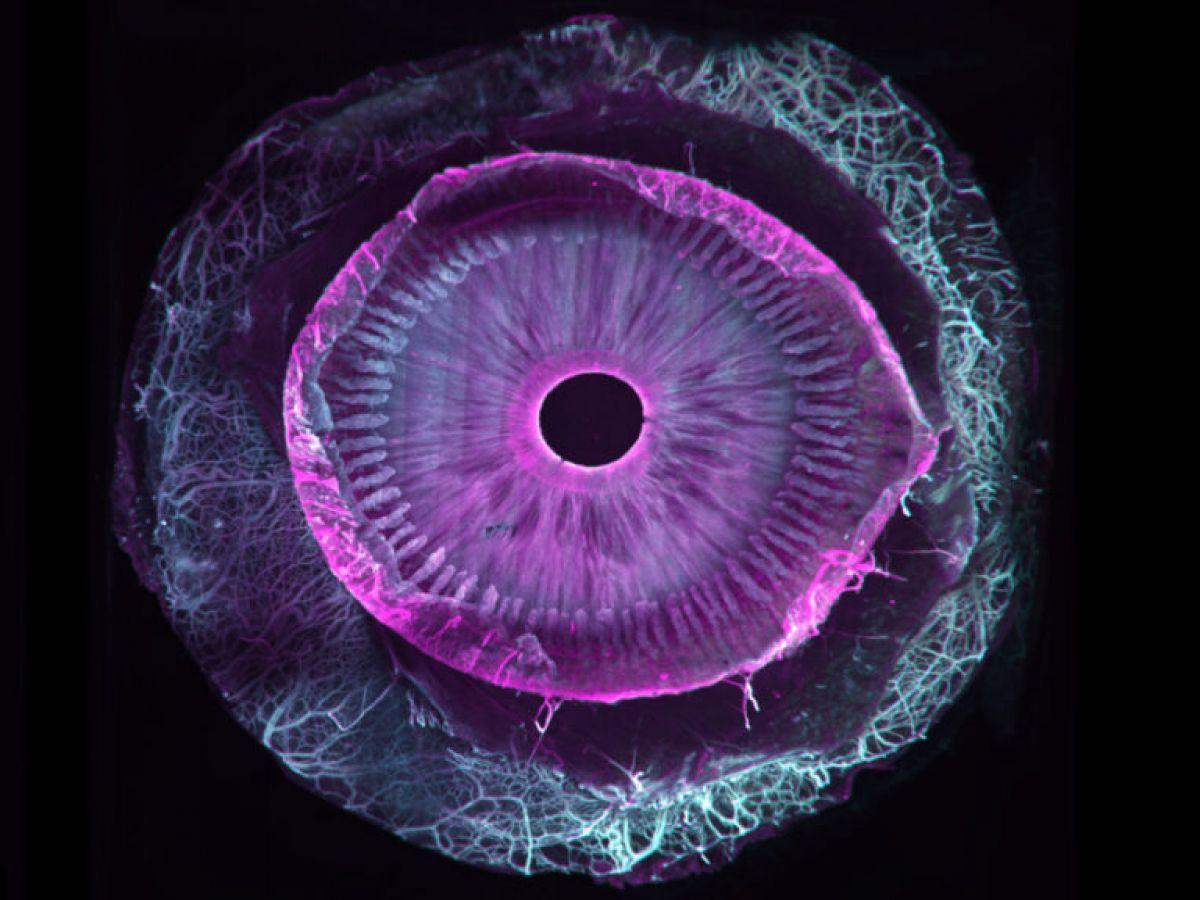

Africa-Press – Cameroun. Sept ans de travail pour une première mondiale : la transparisation (le fait de rendre transparent) d’un œil humain entier. Ce travail, tout juste publié dans la revue Communications Biology, est une collaboration franco-suisse entre, d’une part, Marie Darche, une ingénieure de recherche et membre de l’équipe du Pr Michel Paques à l’hôpital des Quinze-Vingts et à l’institut de la vision (Paris), et d’autre part ses collègues de l’institut Wyss (Genève).

Si les seconds se sont eux occupé du versant imagerie du projet grâce à un dispositif optique particulier, un microscope à feuillet de lumière (MesoSPIM), la biologiste s’est, elle, attaquée au versant « clearing », c’est-à-dire les étapes de transparisation permettant de transformer un échantillon biologique initialement opaque en une structure transparente. Comment ? Par différentes manipulations reposant sur une succession de bains dans des solvants organiques associées au marquage par des anticorps fluorescents.

Tout commence forcément avec des dons d’yeux, issus ici de donneurs américains morts, la législation française ne permettant pas ce type précis de dons (la banque française des yeux ne s’occupe que des cornées et pas d’œil entier). En pratique, toujours de petites sphères de six centimètres cube de volume, dont on ne soupçonne pas l’extraordinaire complexité ni l’hétérogénéité en lien avec les différentes couches de cellules, vaisseaux, nerfs, cellules immunitaires…

Car si d’autres équipes étaient parvenues par le passé à clarifier certains segments de l’œil, c’est bien ici la première fois qu’un œil entier est transparisé. « Au total, nous avons utilisé 25 yeux sains et allons prolonger nos travaux avec d’autres globes oculaires cette fois pathologiques et atteints de DMLA (dégénérescence maculaire liée à l’âge, ndlr), de glaucome et de myopie forte, le tout grâce au soutien d’associations de patients », précise la chercheuse, qui poursuit : « Nos travaux permettront une approche plus holistique des pathologies de l’œil tout comme un meilleur dialogue entre chercheurs et cliniciens pour mieux comprendre les maladies de l’œil et leurs mécanismes ».